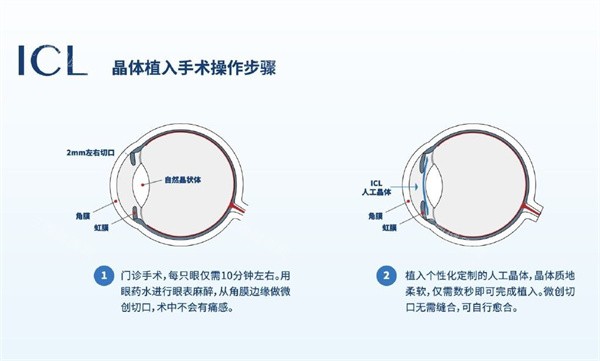

第 1步:麻醉(1分钟)

表面麻醉眼药水+少量球周麻醉,不是"打麻药针"!广州爱尔眼科的刘主管解释:"就像滴普通眼药水,但能让眼睛'麻木'20分钟。"

第2步:做切口(2分钟)

在角膜边缘开3mm小口,比指甲盖还小。北京同 仁医院的张医生比喻:"这就像在鸡蛋壳上开个小窗,既要够大放晶体,又不能伤到'蛋黄'(晶状体)。"

第3步:装晶体(5分钟)

折叠的晶体通过注射器推进眼内,再用调位钩展开。上海新视界眼科的王医生透露:"比较考验技术的是调整角度,散光晶体要精细对齐,差1度都会影响结果。"

第4步:定位(2分钟)

用显微镜观察晶体位置,确认无偏移、无褶皱。杭州明视康眼科的郑主管笑称:"这时候就像给眼睛'戴美瞳',得确保既舒服又好看。"